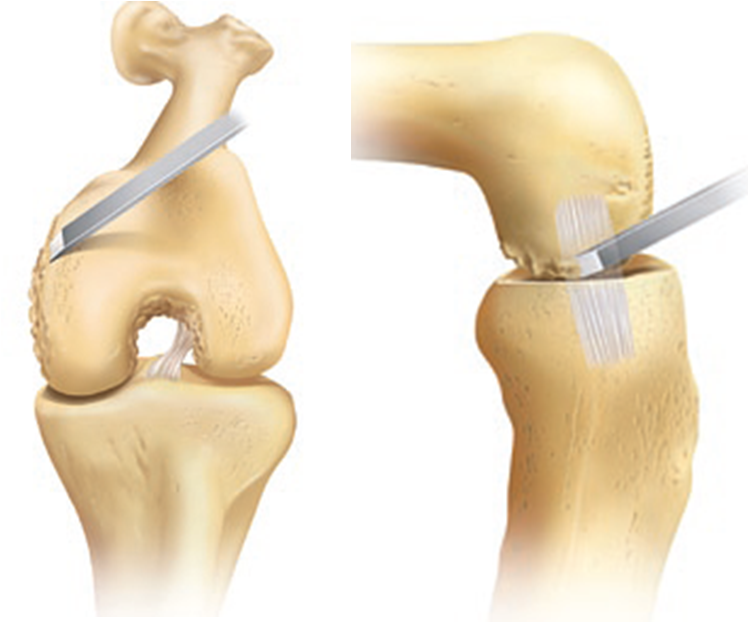

膝关节单髁置换术图解

什么是膝关节单髁置换手术?